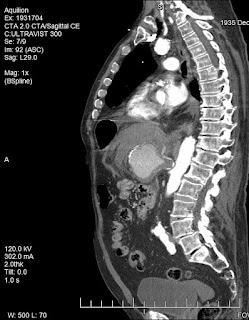

The patient’s initial complete blood count (CBC) demonstrated a white blood cell count of 24.0 x109/L, hemoglobin of 11,000 g/L, platelet count of 198 x109/L, and a left shift (93% neutrophils). The comprehensive metabolic panel (CMP) was unremarkable. Creatine phosphokinase (CPK) and troponin were normal. Amylase and lipase were normal. The patient underwent a computed tomography angiogram (CTA) of the chest and abdomen, which showed an 8.0 x 6.0 x 6.5 cm aneurysm in the location of the celiac artery and splenic artery with extensive fat stranding, representing active hemorrhage.